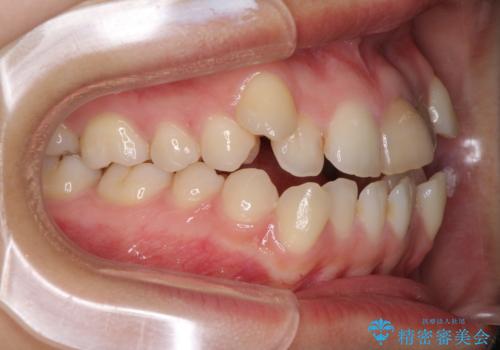

- 上の八重歯を気にして来院された患者様です。

受け口傾向にあるため、上顎前歯の叢生解消とともに下顎前歯を後方へ移動させることを目的とし、上下左右の第一小臼歯4歯を抜歯することとしました。